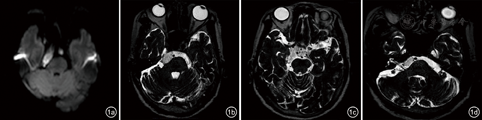

患者,女性,57岁。因"发作性右侧面部疼痛30年"入院。入院检查:神志清楚,语言流利,瞳孔等大等圆,对光反射灵敏,活动自如。右侧鼻翼及鼻翼旁触痛阳性。额纹对称,鼻唇沟等深,伸舌居中,颈软。四肢活动自如。初步诊断为颅内占位:右侧胆脂瘤?右侧继发性三叉神经痛(v2、v3)。MR示右侧鞍区及脑干区域幕下占位,胆脂瘤可能(图1)。